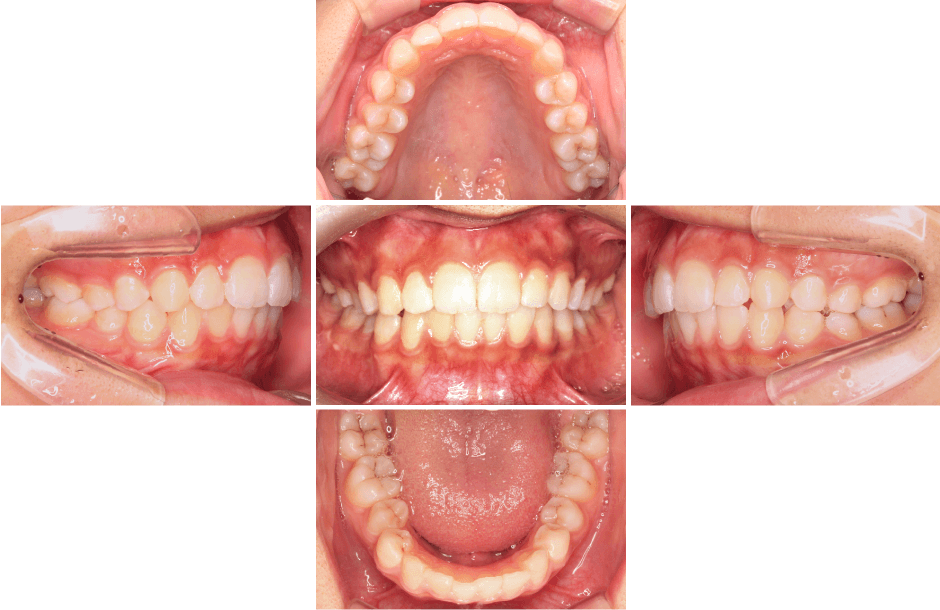

| 主訴 | ガタガタの歯並びを治したい |

|---|---|

| 治療内容 |

マウスピース型矯正装置(インビザライン)

両側クラスⅠ 叢生

|

| 年齢 | 12〜14歳 |

| 治療期間、回数 |

1年10ヶ月(2019年9月〜2021年7月) 16回 |

| 費用 |

検査費:110,000円(税込) 基本料:990,000円(税込) 調整代:3,300 円(税込) |

| リスク、 副作用 |

・歯を動かすのに痛みを伴う ・マウスピースを20時間以上入れていなかったため、計画に遅れが出る ・虫歯と歯周病の管理を怠ると、進行するリスクが上がる ・重度の叢生であるため、歯肉が下がるリスクがある |

| 担当医 | 石川 健 |